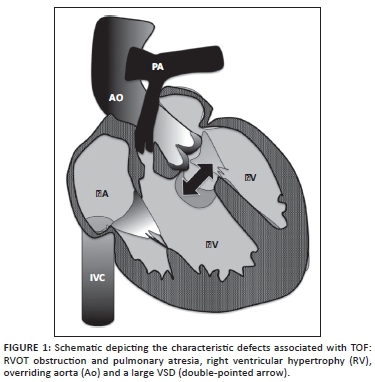

The earliest reports of the anomaly are, however, attributed to Niels Stensen (1671), Edouard Sandifort (1777) and William Hunter (1784), amongst many others. Etienne-Louis Arthur Fallot published five serialised reports in the Marseille Medical in 1888 in which he described his now famous 'blue malady'. Whilst Fallot described the classical tetrad of pulmonary outflow tract obstruction, ventricular septal defect (VSD), aortic override and right ventricular hypertrophy (RVH) (Figure 1), Stella Van Praagh in 1970 attributed the anomaly to a single defect of pulmonary valve and subpulmonary infundibular malformation, the so-called 'monology of Stensen'.1 The diagnostic and surgical consequences of this realisation have resulted in improved long-term patient survival.